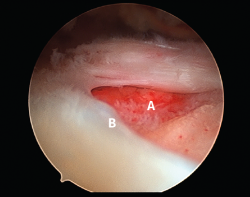

Figura 1. Rotura en forma creciente. A: acromion; B: rotura en forma de semiluna del tendón supraespinoso.

Figura 5. Rotura de tipo C1. A: rotura pequeña de espesor completo del supraespinoso; B: cabeza humeral.

Sin embargo, las clasificaciones basadas en el tamaño de la rotura deben ser bidimensionales, ya que la visión unidimensional puede ser engañosa, al mostrar el tamaño de la rotura solo desde el plano anteroposterior(4). Por esta razón, proponemos el sistema de clasificación del manguito posterosuperior sugerida por Snyder, que aporta información no solo del tamaño, sino del número de tendones afectados y la presencia de tejido cicatricial(7). En las lesiones de tipo C1 la lesión atraviesa todo el espesor del tendón y en el eje transversal es pequeña y punzante (Figura 5). Las de tipo C2 son roturas de espesor completo pero la distancia entre los extremos de la rotura es menor de 2 cm con escasa retracción (Figura 6). En las de tipo C3 la rotura afecta en sentido transversal entre 3 y 4 cm con mayor retracción implicando 2 tendones (Figura 7). Y las de tipo C4 son la rotura masiva del manguito de los rotadores con una afectación de espesor completo de toda la anchura de 2 o más tendones asociando importante retracción (Figura 8).